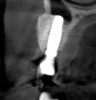

Tomographic images revealed a large tridimensional defect, with vertical and horizontal loss of bone extending to the apical third of teeth Nos. 6 and 8. Additionally, a buccal bone dehiscence was evident on tooth No. 5, and thin labial plates secondary to the orthodontic movement were present in several areas (Figure 3 and Figure 4).

Fig 4. Tomographic images revealed a tridimensional defect extending to the apical third of teeth Nos. 6 and 8, a buccal bone dehiscence on tooth No. 5, and associated thin labial plates.

Figure 4